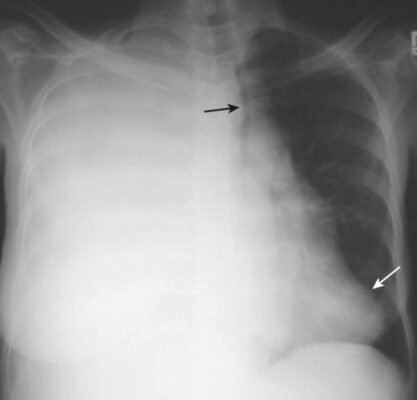

- Để thực hiện phẫu thuật này, thường cần cắt bỏ xương sườn thứ 5 hoặc thứ 6 ở bên bị ảnh hưởng. Trong hầu hết các trường hợp, có thể thấy các kẹp phẫu thuật bằng kim loại ở vùng rốn phổi ở phía bên phổi bị cắt bỏ.

- Trong khoảng 24 giờ sau cuộc phẫu thuật, chỉ có không khí chiếm giữ nửa vùng phổi bị lấy bỏ (Hình 7).

- Trong vòng 2 tuần tiếp theo, nửa phổi dần dần được lấp đầy bởi chất dịch.

- Khoảng 4 tháng sau khi phẫu thuật, vùng ngực bị lấy bỏ phổi sẽ hoàn toàn mờ đục.

- Cuối cùng, các mô xơ hình thành trong vùng ngực bị lấy bỏ phổi, và ở hầu hết các bệnh nhân, toàn bộ nửa lồng ngực hoàn toàn mờ đục. Tim và khí quản dịch chuyển về phía bị mờ.

- Khám ngực giống như khám của một bệnh nhân bị xẹp phổi toàn bộ. Để nhận biết sự khác biệt, hãy tìm xương sườn thứ 5 hoặc thứ 6 bị thiếu và tìm kiếm các kẹp phẫu thuật ở rốn phổi để chứng tỏ phẫu thuật cắt bỏ phổi đã được thực hiện (Hình 8).